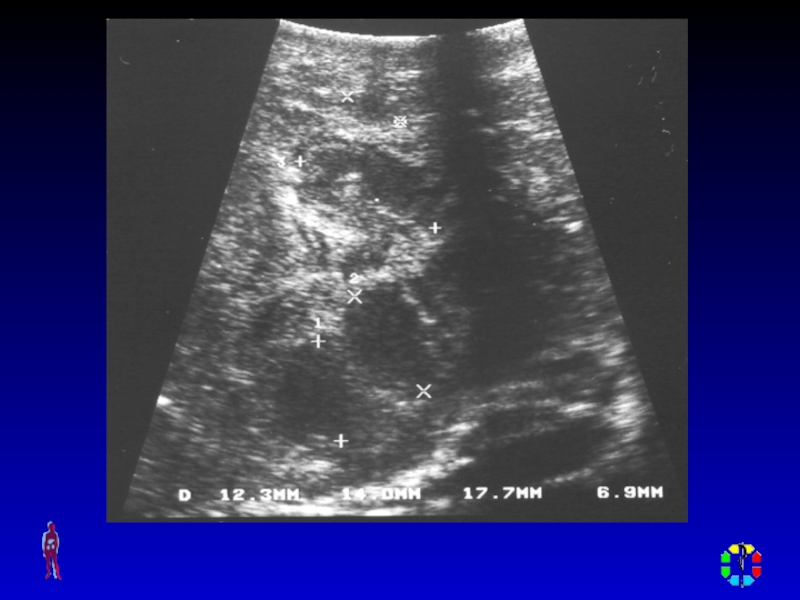

Слайд 22ДИАГНОСТИКА

Диагностическая пункция

УЗИ мягких тканей, рентгенологическое исследование , КТ,

радиоизотопное исследование.

ДИАГНОСТИКА Диагностическая пункция УЗИ мягких тканей, рентгенологическое исследование , КТ, радиоизотопное исследование.